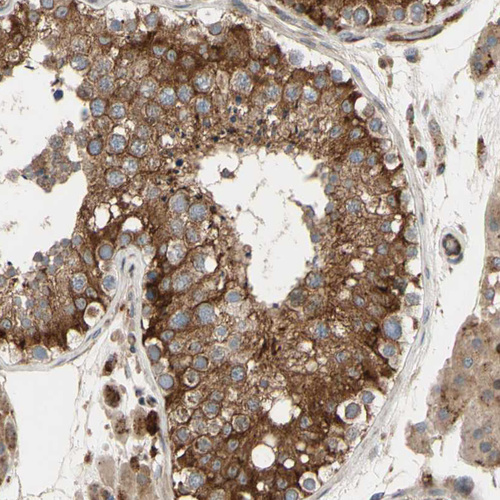

Immunohistochemical staining of human rectum shows strong cytoplasmic positivity in glandular cells.